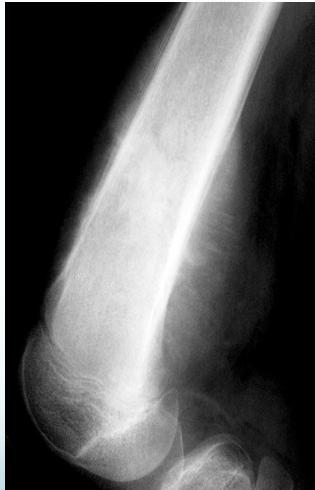

Radiological Features

- X-ray:

- Radiolucency and sclerosis

- Poorly defined margins

- Extends into soft tissue

- Periosteal reaction:

- Sunburst (sun-ray) appearance

- Codman’s triangle